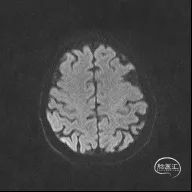

颅脑MR:脑内多发缺血灶、软化灶。